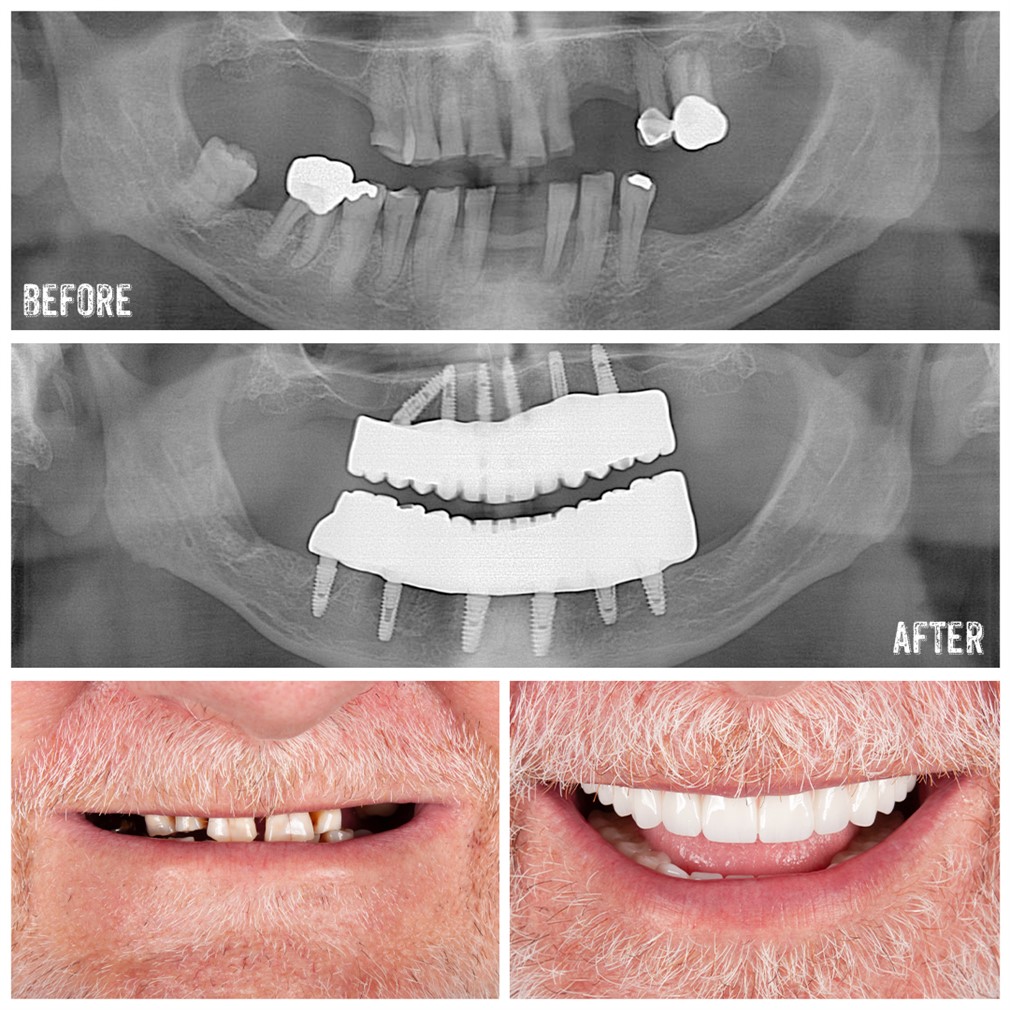

All-on-4 treatment, which has become quite popular in modern dentistry, offers many advantages for patients as an implant treatment method. This treatment option is faster, more economical, and more effective compared to traditional implant treatments, especially for patients who are completely edentulous or at risk of becoming completely edentulous in the near future.

Implantation is one of the methods developed to replace lost teeth due to chewing, taste perception, speech, pain, and aesthetics. However, implant treatment tends to be more prolonged and costly for patients who are completely edentulous or at risk of becoming completely edentulous in the near future. All-on-4 treatment is a rapid and effective treatment method aimed at eliminating the need for advanced surgery due to sinus lift, bone addition, and insufficient bone in patients who are completely edentulous.

The All-on-4 treatment concept involves the fixed full-jaw prosthetic restoration on 4-6 implants placed in the same surgical operation. Considering function, aesthetics, taste, speech, and confidence, it ensures patient satisfaction.

The All-on-4 treatment utilizes the titanium screw mechanism used in traditional implants. The most significant difference between traditional implants and All-on-4 implants lies in how they are positioned within the mouth. While 8 or 10 implants are typically used to replace missing teeth in a completely edentulous jaw, this new technique requires only 4 implants.

In the anterior region, 2 implants are placed where the bone is thickest, while in the posterior part of the jaw, 2 implants are placed. The implants in the front are positioned at a 90-degree angle, while those in the back are placed at a 45-degree angle to maximize strength. After these 4 implants are placed, bridges or crowns are fitted onto them.

Temporary prostheses are prepared based on measurements taken from patients before the All-on-4 treatment. If there are any teeth to be extracted, they are removed under local anesthesia, and the implants are placed. Temporary prostheses prepared based on measurements are then attached to these implants. After 3 months, the patient's permanent prostheses are fitted.